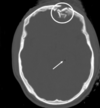

Based off of the imaging, what is the most likely diagnosis?

Epilepsy

Haemorrhage

Hydrocephalus

Normal

A